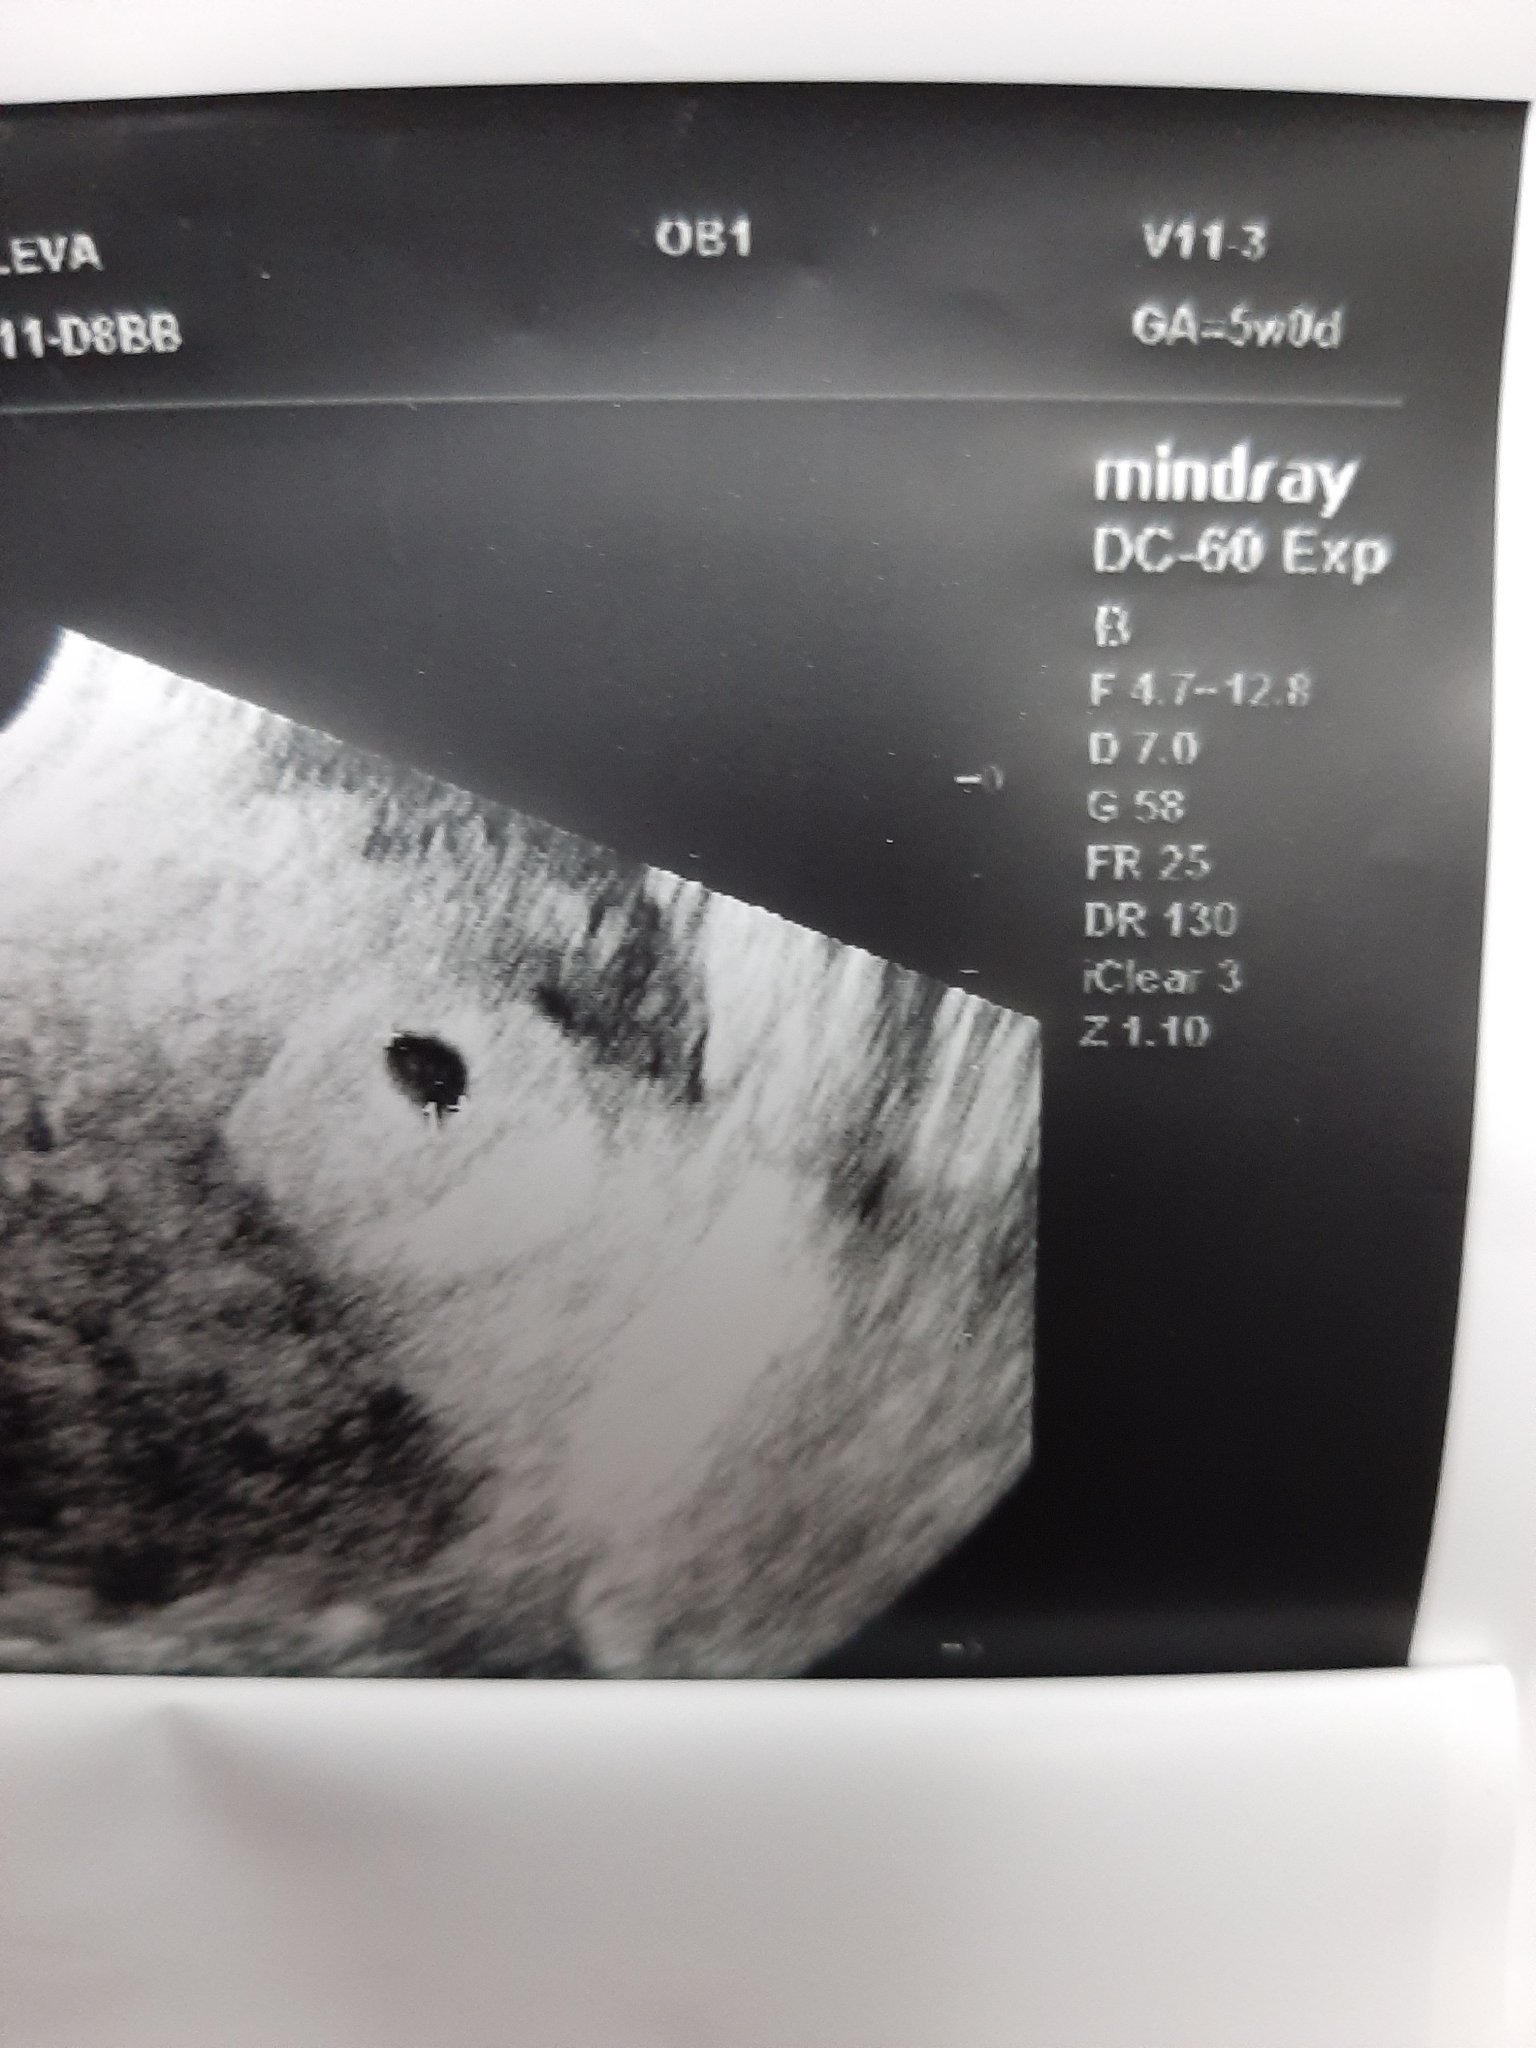

Здравейте преди малко се върнах от лекар, каза ми че отг на петата г.с обаче не вижда ембрион възможно ли е да е твърде рано да се види ембриона?

Сак се е видял, доколкото разбирам, за ембрион е още рано. При мен в 5 г.с. се видя сак с жълтъчен мехур. Две седмици по-късно имаше ембрион с пулс.

Radostina21, запази спокойствие колкото можеш. На мен също в 5 гс докторката каза, че не се вижда нищо и да изчакаме още поне една седмица и пак да отида, така и направих в 6+3 гс вече имаше жълтъчно мехурче и ембрион точица. Прикачвам ти и моите снимки, надявам се малко да те окуража